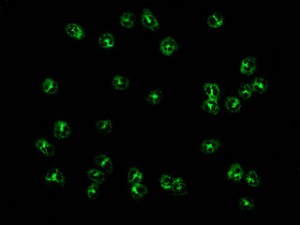

Image of the Month – Past Images

What is Rheumatology?

Rheumatologists see over 100 different types of diseases. We are known for seeing arthritis, however, we also see many other conditions.